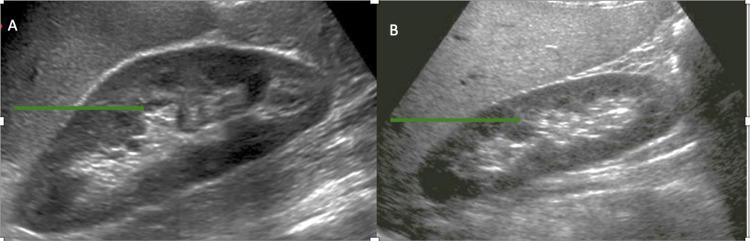

Kidneys influence the production of red blood cells by secreting most of the erythropoietin (EPO) in adults. Consequently, renal diseases often impact erythropoiesis and hemoglobin levels. Chronic kidney diseases lead to anemia due to EPO deficiency. However, erythrocytosis can occur in patients with cystic diseases of the kidney and renal artery stenosis due to upregulation of hypoxia-inducible factors (HIFs) and increased EPO production. Here, we present a patient with secondary polycythemia who was found to have atonic bladder and hydronephrosis. Resolution of hydronephrosis led to the reversal of erythrocytosis, highlighting the intricate regulation of red cell production.

在成年人中,肾脏通过分泌大部分促红细胞生成素(EPO)来影响红细胞的生成。因此,肾脏疾病常常会影响红细胞生成和血红蛋白水平。慢性肾脏疾病会因EPO缺乏导致贫血。然而,由于缺氧诱导因子(HIFs)上调和EPO生成增加,患有肾囊性疾病和肾动脉狭窄的患者可能会出现红细胞增多症。在此,我们报告一名患有继发性红细胞增多症的患者,该患者被发现存在无张力膀胱和肾积水。肾积水的缓解导致红细胞增多症的逆转,突出了红细胞生成的复杂调节机制。